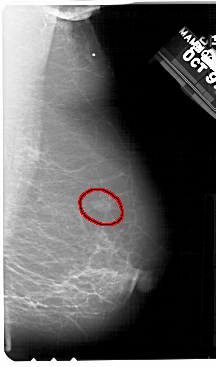

A_1357_1.RIGHT_CC

RIGHT_CC LINES 5491 PIXELS_PER_LINE 2371 BITS_PER_PIXEL 12 RESOLUTION 43.5 OVERLAY

FILE: A_1357_1.RIGHT_CC.OVERLAY

TOTAL_ABNORMALITIES 1

ABNORMALITY 1

LESION_TYPE MASS SHAPE OVAL MARGINS ILL_DEFINED

ASSESSMENT 4

SUBTLETY 3

PATHOLOGY BENIGN

TOTAL_OUTLINES 1

BOUNDARY